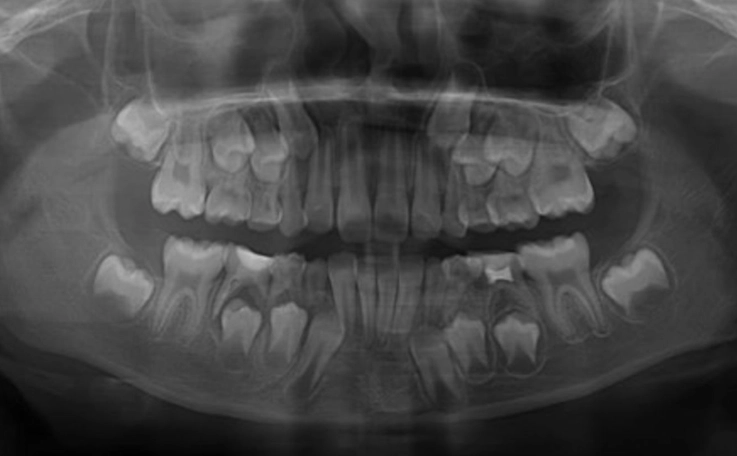

Why a Regular Dental X-Ray Often Isn't Enough

Your dentist's 2D X-ray is a fantastic first tool. It's cheap, fast, and shows a lot. It can often show a dark, rounded area at the root tip, suggesting an abscess. But it has a major flaw: it compresses a complex 3D structure into a flat image.

This is where the periapical abscess CT scan, specifically a CBCT (Cone Beam CT) designed for dentistry, becomes the game-changer.

Let's put it all side-by-side. This table shows why a periapical abscess CT is reserved for specific, complex situations.

| Imaging Type | What It Shows (For Abscess) | Key Advantages | Key Limitations | Best Used For |

|---|---|---|---|---|

| Periapical X-ray | 2D view of 2-3 teeth, bone level, obvious large abscess. | Low cost, low radiation, readily available, good for initial detection. | Compression of anatomy, no 3D data, can miss size, shape, and relationships. | Initial screening, monitoring healing post-treatment. |

| Panoramic X-ray | Broad 2D view of entire jaw, teeth, sinuses, jaw joints. | Great for big-picture view, spotting other issues, low-ish radiation. | Blurry detail, distortion, still no 3D information. Poor for fine abscess anatomy. | Initial comprehensive exam, evaluating wisdom teeth, jaw fractures. |

| Cone Beam CT (CBCT) | 3D, detailed, slice-by-slice view of bone, tooth roots, abscess shape, sinus/nerve proximity. | Unmatched detail for complex anatomy. Essential for surgical planning. Reduces surprises. | Higher cost, higher radiation than X-rays (but lower than medical CT), not needed for simple cases. | Complex abscesses, re-treatment cases, suspected fractures, pre-surgical planning (apicoectomy). |

See the difference? The CBCT is the specialist's tool. It's not for every toothache. But when the situation is murky or high-risk, it provides clarity that nothing else can.